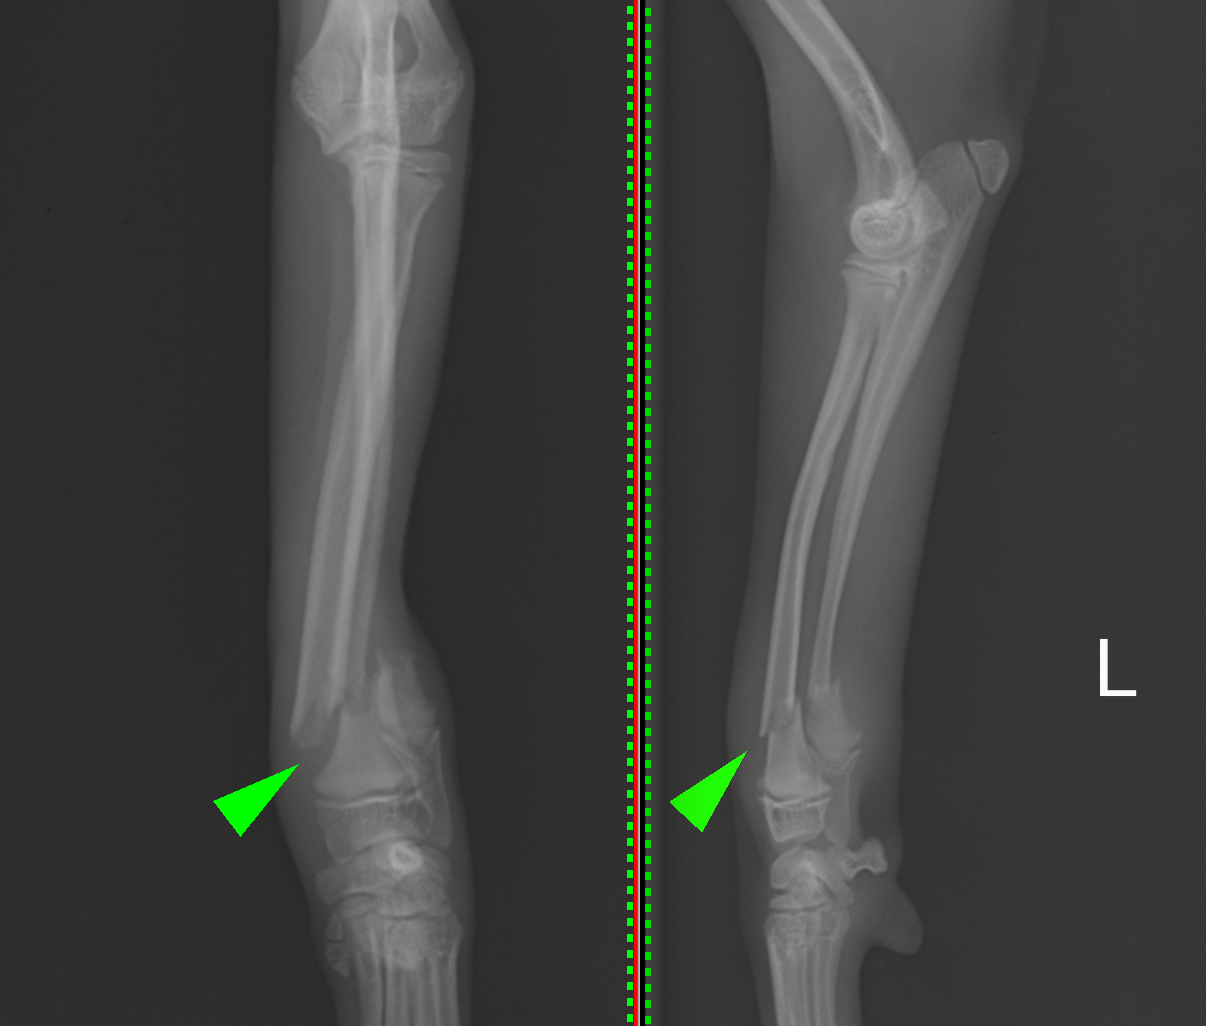

2025年6月22日開催の第110回日本獣医麻酔外科学会学術集会にて磯野がパテラ(膝蓋骨内方脱臼)の形態学的変化についての発表を行いました。CT画像をもとに脛骨の形態学的変化についてご説明させていただきました。

整形外科の雑誌であるVeterinary and Comparative Orthopaedics and Traumatologyに磯野の論文である「Tibial Torsion Malalignment in Small Dogs with Medial Patellar Luxation」が掲載されました。パテラ内方脱臼に対し、脛骨粗面と足根骨の捩れが関与しているをことを示し、その指標の一つを提言した内容になります。ご興味ある方はご覧ください。